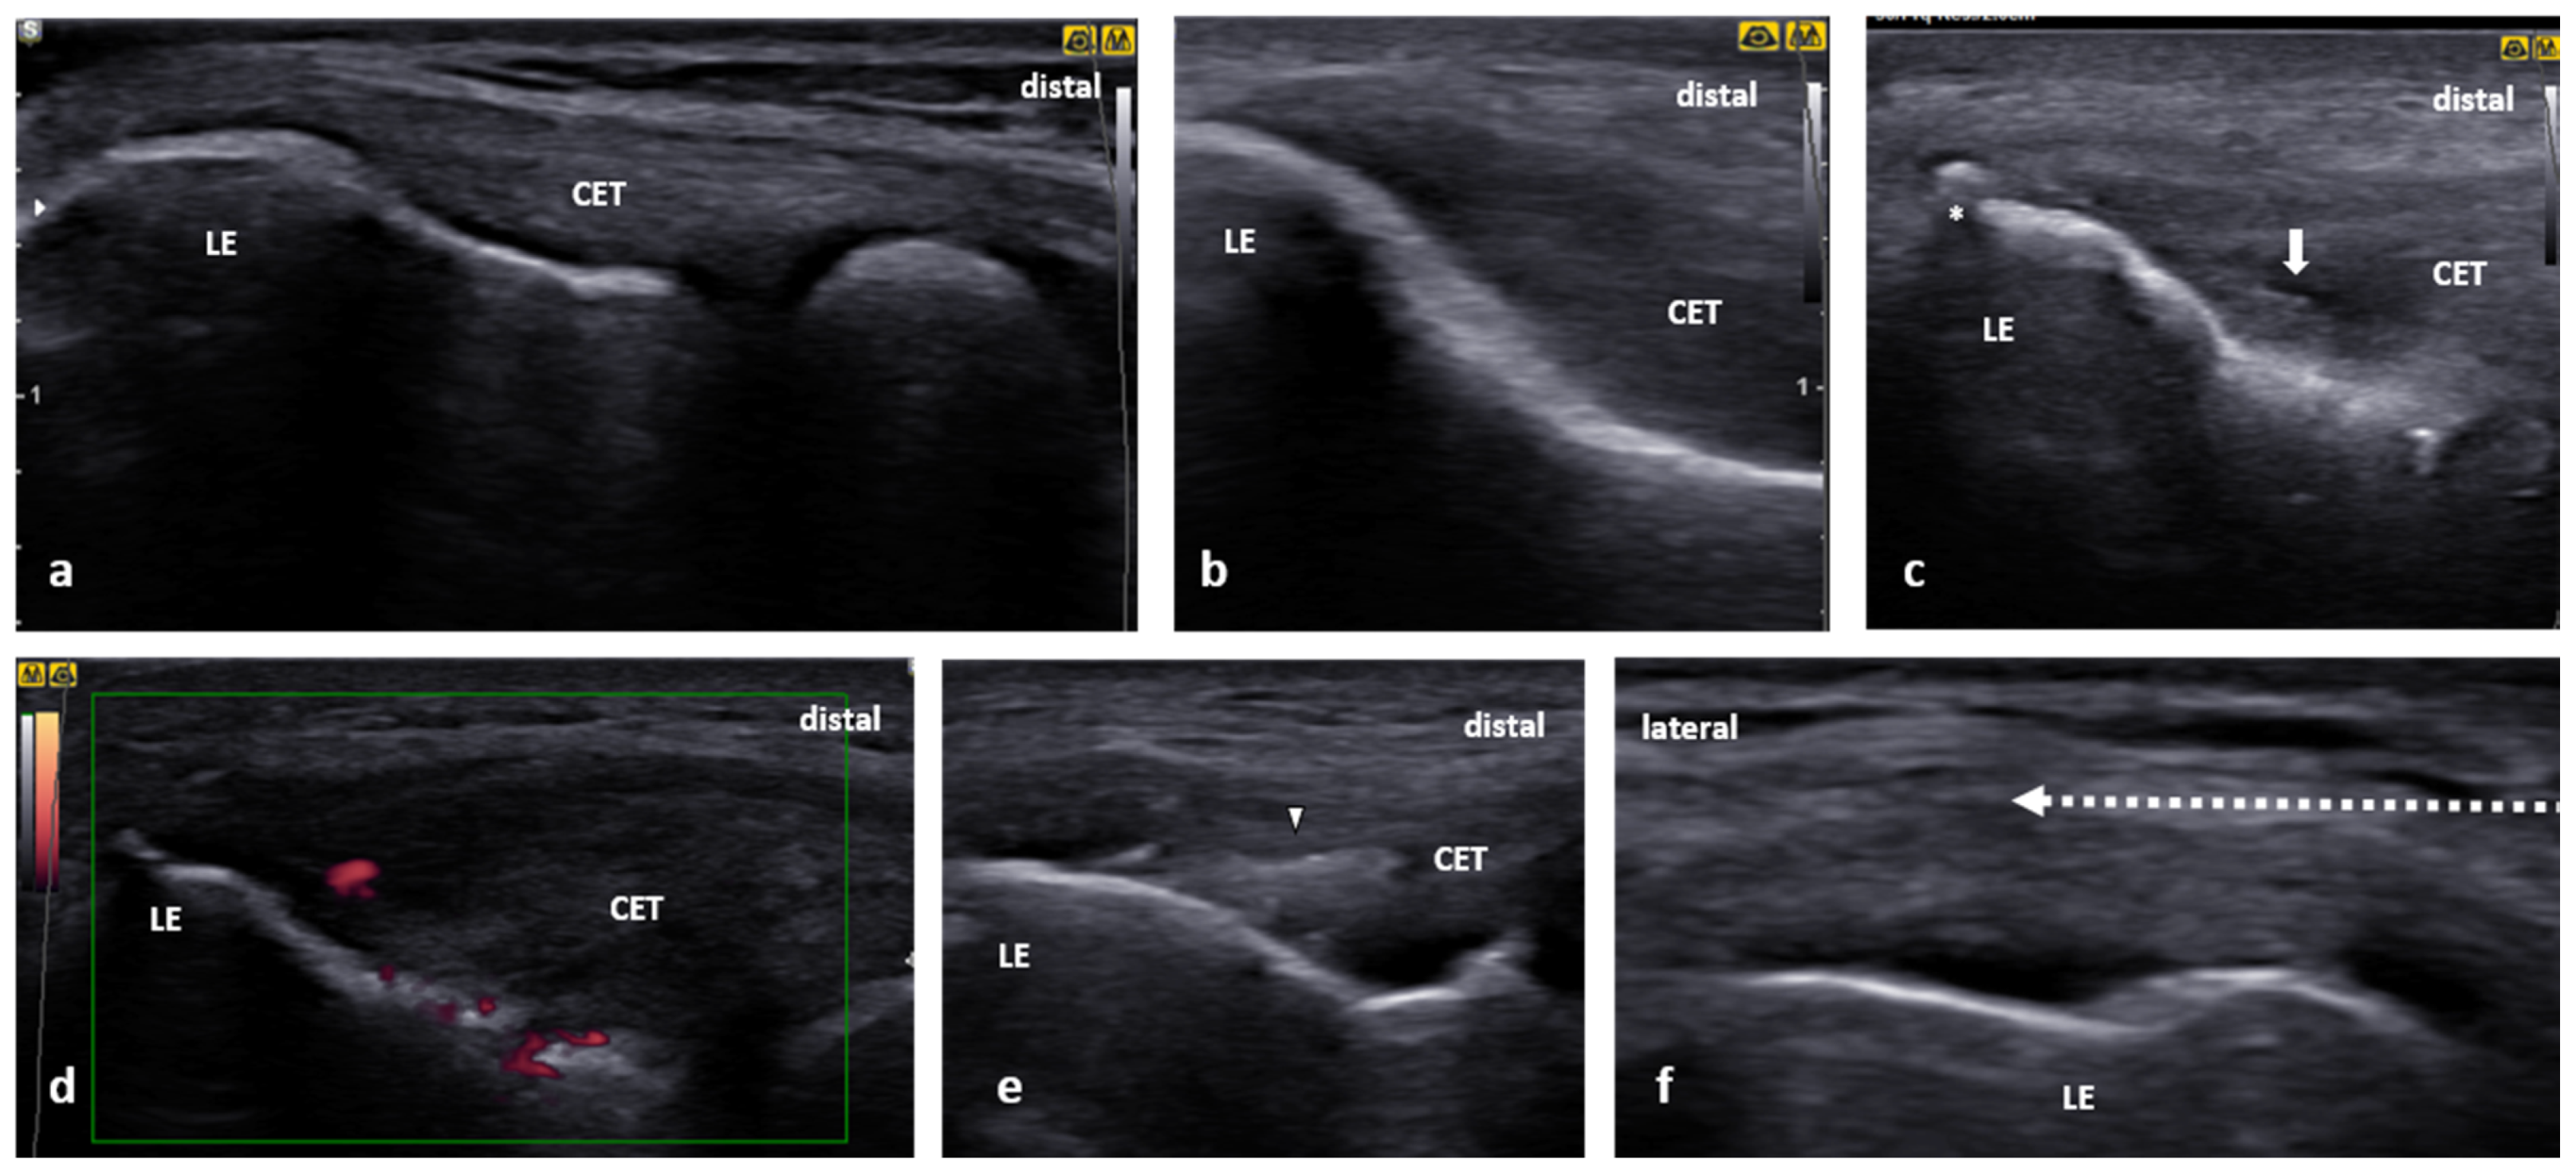

When intact, the CET is noncompressible, homogenous, and hyperechoic with a fibrillar tendinous pattern (Figure 4a). In pathologic cases, the examiner can observe cortical irregularities (e.g., bony spurs or erosions), tendon thickening with a loss of normal fibrillar pattern, focal or diffuse hypoechogenicity, calcifications, tears, and hypervascularity (Figure 4b–e) [36]. Furthermore, the examiner can use sonopalpation to correlate the abnormal findings with local tenderness [37].

Figure 4.

Ultrasound (US) images of the CET: (a) normal image, (b) a simple thickening and hypoechogenicity of the CET, (c) US image demonstrating a prominent spur (white asterisk) on the tip of the lateral epicondyle (LE) and focal hypoechogenicity in the tendon (white arrow), (d) a severe swelling of the CET with increased vascularity on power Doppler, (e) a mild swelling of the CET with intrasubstance hyperechogenicity indicating an immature calcification (white arrowhead) without acoustic shadowing, and (f) a US-guided peritendinous CET injection showing the needle (white, dotted arrow) being inserted from medial to lateral in a short axis of the CET.

One of the technical variants to perform the tennis elbow injection is the same as for the examination in the supine position. The transducer is positioned on the lateral epicondyle perpendicular to the long axis of the forearm. The needle is inserted from lateral to medial (Figure 4f). Depending on the particular procedure plan, the needle tip can reach the peritendinous space or the tendon itself to perform intralesional (e.g., PRP) injection. The approach mentioned above allows the needle course to be parallel to the probe thus providing excellent needle visibility. Alternatively, the needle can be administered from distal to proximal (Supplementary Materials Video S1) or vice versa. When injecting the tennis elbow, potentially vulnerable structures include the anterior branch of the deep brachial artery and the deep branch of the radial nerve. Using US guidance can reduce the risk of iatrogenic injury to the structures mentioned above.